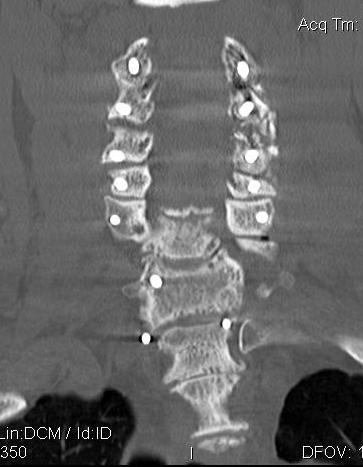

CT

Helps distinguish disc from osteophytes

- soft v hard disc

- diagnose OPLL

OPLL on CT

MRI and CT in same patient with OPLL